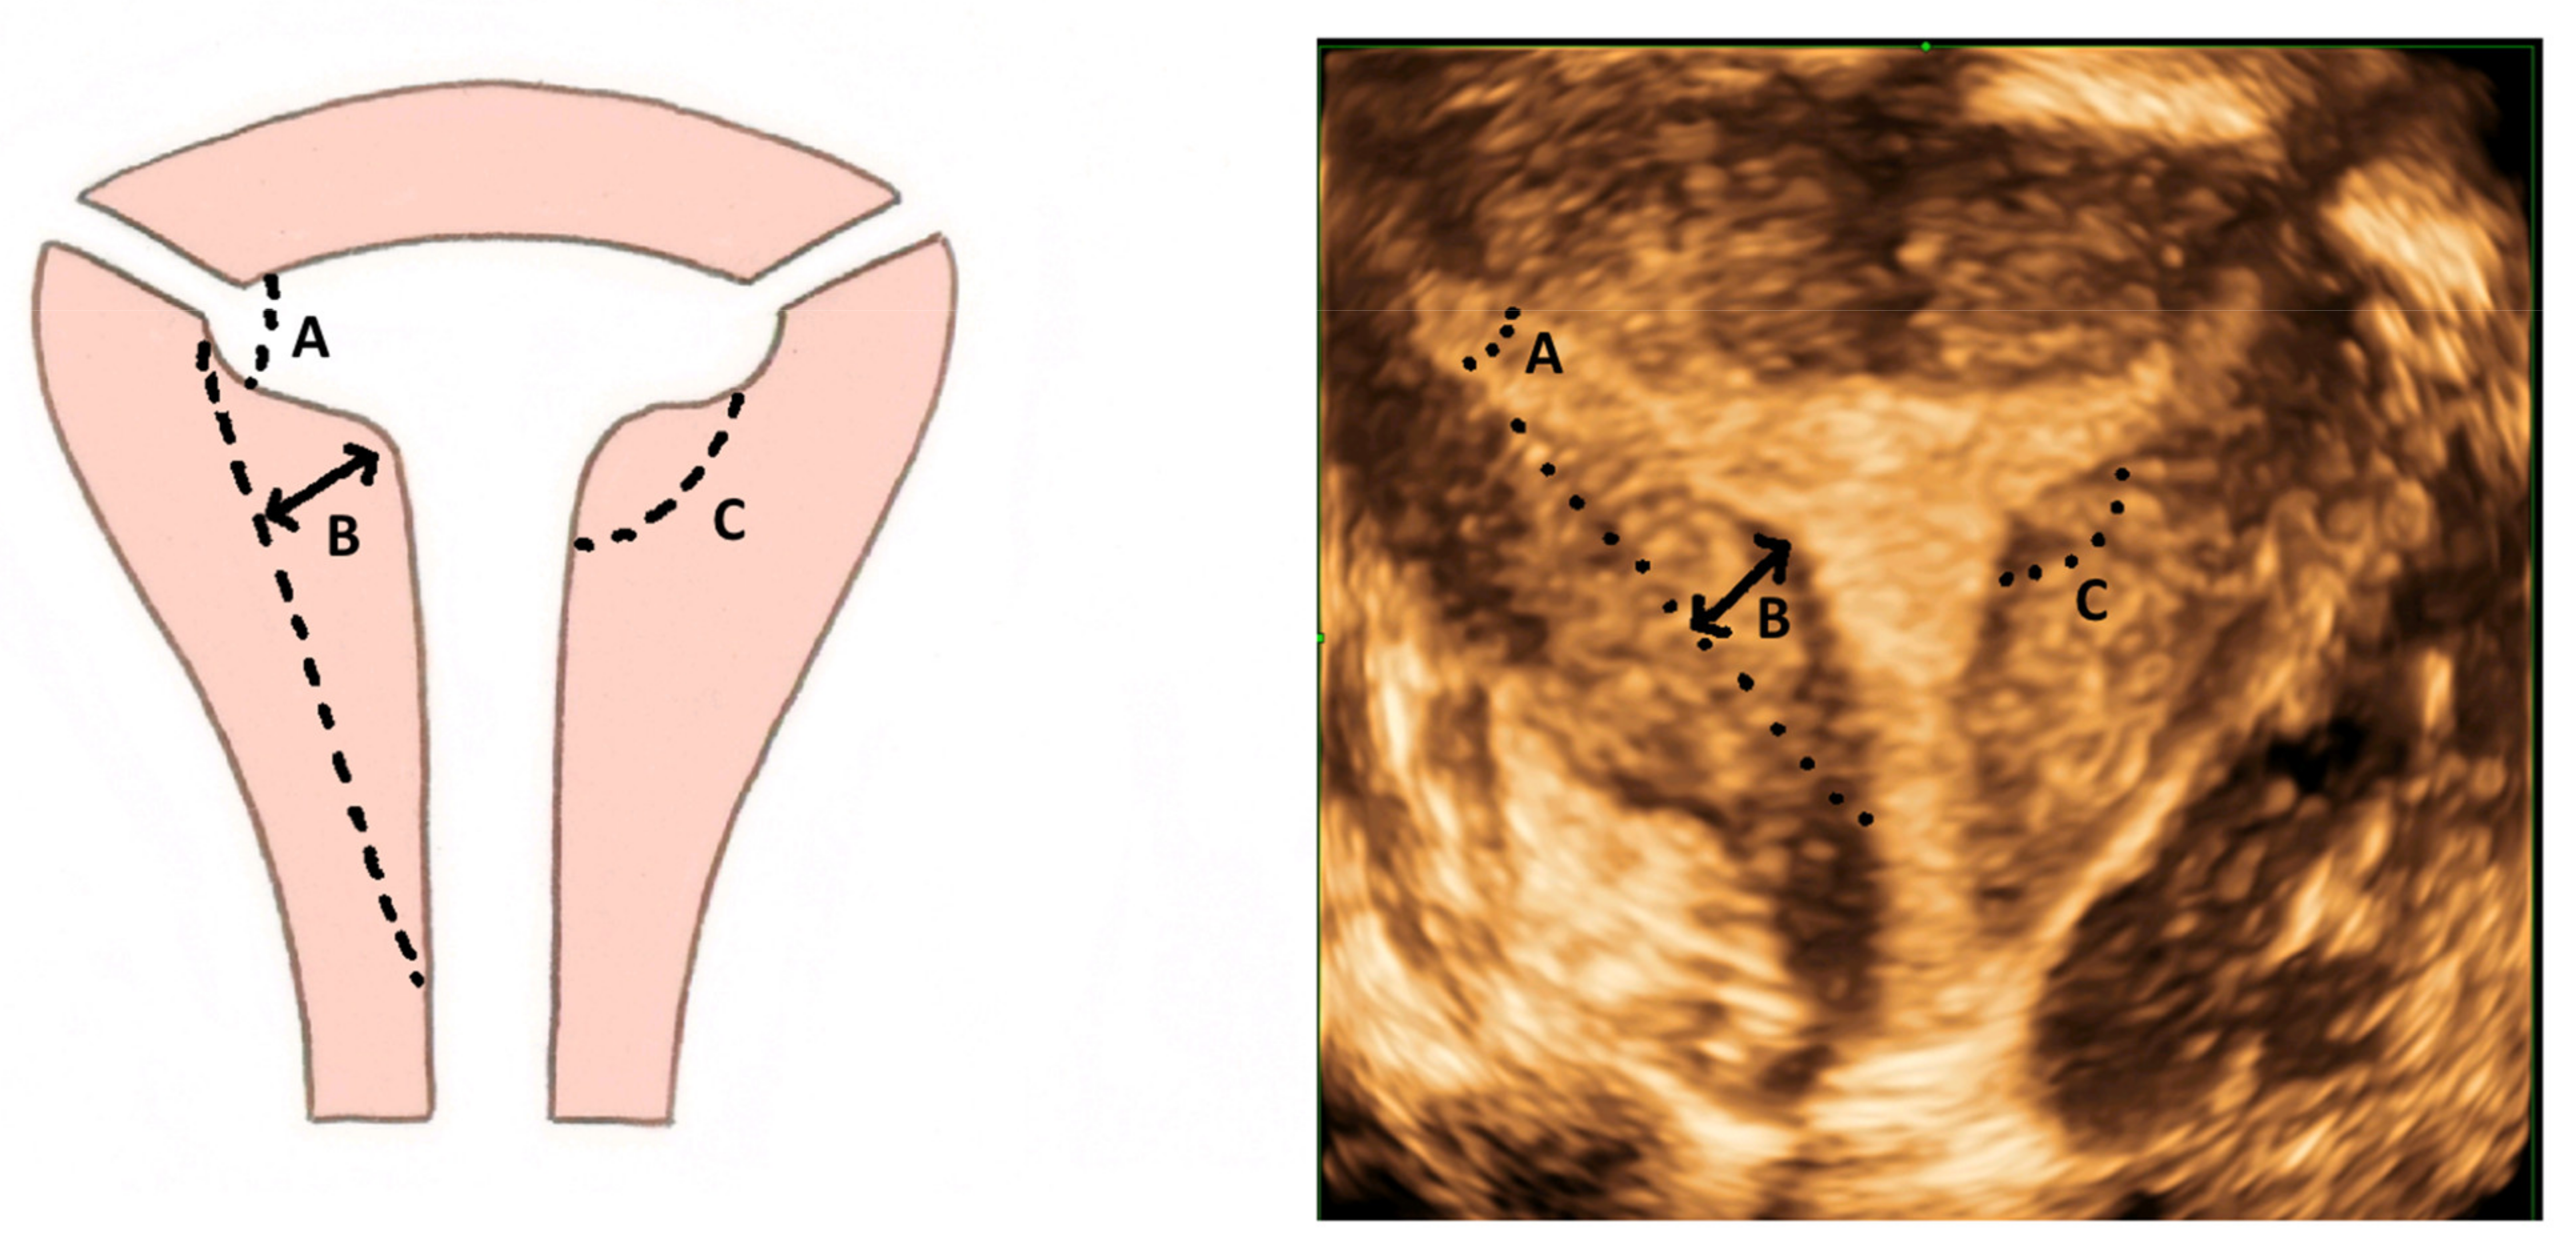

The diagnostic accuracy of 3D ultrasound compared with laparoscopy ± hysteroscopy in diagnosing CUA is highest among other imaging modalities including MRI. The diagnostic accuracy of 3D ultrasound is reported as 97.6% with sensitivity and specificity of 98.3% and 99.4%, respectively [18]. The morphology of the uterus is best examined in the coronal plane (Figure 8) using the interstitial portions of the fallopian tubes as reference points. A line joining the tubal ostia (interostial line) is the reference line (Figure 9). A parallel line on top of the fundus can be drawn and the vertical distance between this line and the interostial line is the uterine wall thickness. In cases of septate uterus, a parallel line along the apex of the internal midline indentation is drawn and its vertical distance from the interostial line is the septal length. The vertical distance between the parallel line along the bottom (apex) of the external indentation and interostial line is the depth of the external cleft in cases of partial bicorporeal (bicornuate) uterus.

The classification utilising 3D ultrasound based on the publication by Salim et al. (2003) is described in Table 2 [14]. The ESHRE/ESGE classification of uterine anomalies based on the 3D scan assessment is based on using uterine wall thickness as the reference. An internal indentation at the fundal midline of more than 50% of the uterine wall thickness is used to diagnose a septate uterus. On the other hand, a bicorporeal (bicornuate) uterus is diagnosed when the external indentation is more than 50% of the uterine wall thickness. The ASRM in the publication ‘Uterine septum: a guideline’ has suggested diagnosis of normal or arcuate uterus when the distance between the interostial line to the apex of indentation is less than 1 cm and the angle of indentation is more than 90° [19]. It also reported an arcuate uterus as a normal variant and clinically irrelevant. A septate uterus is diagnosed when the indentation depth is more than 1.5 cm and the angle of indentation less than 90°. A bicornuate uterus is diagnosed when the external fundal indentation is more than 1 cm.

The Congenital Uterine Malformation Experts (CUME) group has been critical of the ESHRE/ESGE criteria as overestimating and the ASRM criteria as underestimating the prevalence of septate uterus [9]. In a diagnostic accuracy study using 3D ultrasound, the proportion of septate uteri using the ESHRE/ESGE classification was demonstrated to be higher than using the ASRM criteria (RR 13.9; 95% CI 5.9–32.7, p ≤ 0.01) [20]. The concern about overdiagnosis is that it may lead to increased surgical intervention. The CUME group proposed a definition to diagnose septate uterus as an internal indentation of more than 10 mm, an angle of septal indentation of <140° and an indentation to the uterine wall thickness (I–WT) ratio of >110%. They proposed to use the septal indentation of >10 mm alone as the simplest and most reproducible criteria, if used alone. A summary of the criteria for diagnosing a septate uterus is detailed in Table 5.

While the T-shaped uterine cavity is diagnosed subjectively by some authors, the ESHRE/ESGE has suggested diagnosis based on a narrow uterine cavity due to thickened lateral walls without specifying a definition and cut-off for thickened lateral walls and narrow uterine cavity [21]. The CUME group proposed a lateral indentation angle ≤ 130°, lateral indentation depth ≥ 7 mm and T-angle ≤ 40° as the criteria for diagnosing a T-shaped uterus (Figure 10) [22].

Figure 10. Criteria for diagnosing T-shaped uterus according to CUME ([22]). A—T-angle ≤ 40°; B—lateral indentation depth ≥ 7 mm; C—lateral indentation angle ≤ 130°.